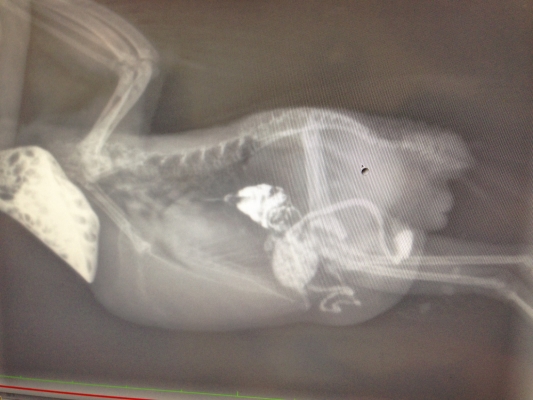

卵巣は確かに腫れてますね、獣医師の診断通り、ヘルニアはあっても軽度なようですね。

やっぱり、発情抑制ですね。ジルバさんのルナちゃんも13歳ですが

卵巣が腫れていて軽くヘルニアになっているようです。

お薬での治療になりました。

腺胃は大丈夫でした。という事は、クリプトスポリジウム

はシロと考えても大丈夫でしょうか?

クリプトスポリジウムの事は、先生にまだ聞いてないので

すが、糞の検査では寄生虫・細菌は問題ないとの事でした。

結局、レントゲンを2回も撮った訳ですが、割と平気

だったみたいです。やっぱりココ様は強いです(笑)